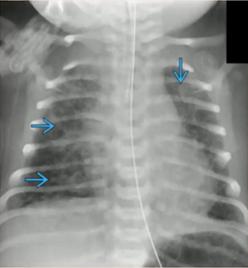

②细菌性与病毒性感染的鉴别

细菌性感染(支气管性肺炎):表现为沿着支气管分布的阴影;弥漫性毛绒状、边界不清,可延续到肺边缘;可伴有胸膜积液、空洞。

病毒性感染(间质性肺炎):表现为沿肺门分布的间质阴影;肺叶过度充气,表现为横膈膜变平;支气管增厚;可伴有分泌物阻塞导致局部不张。

图10.支气管性肺炎(左)与间质性肺炎(右)